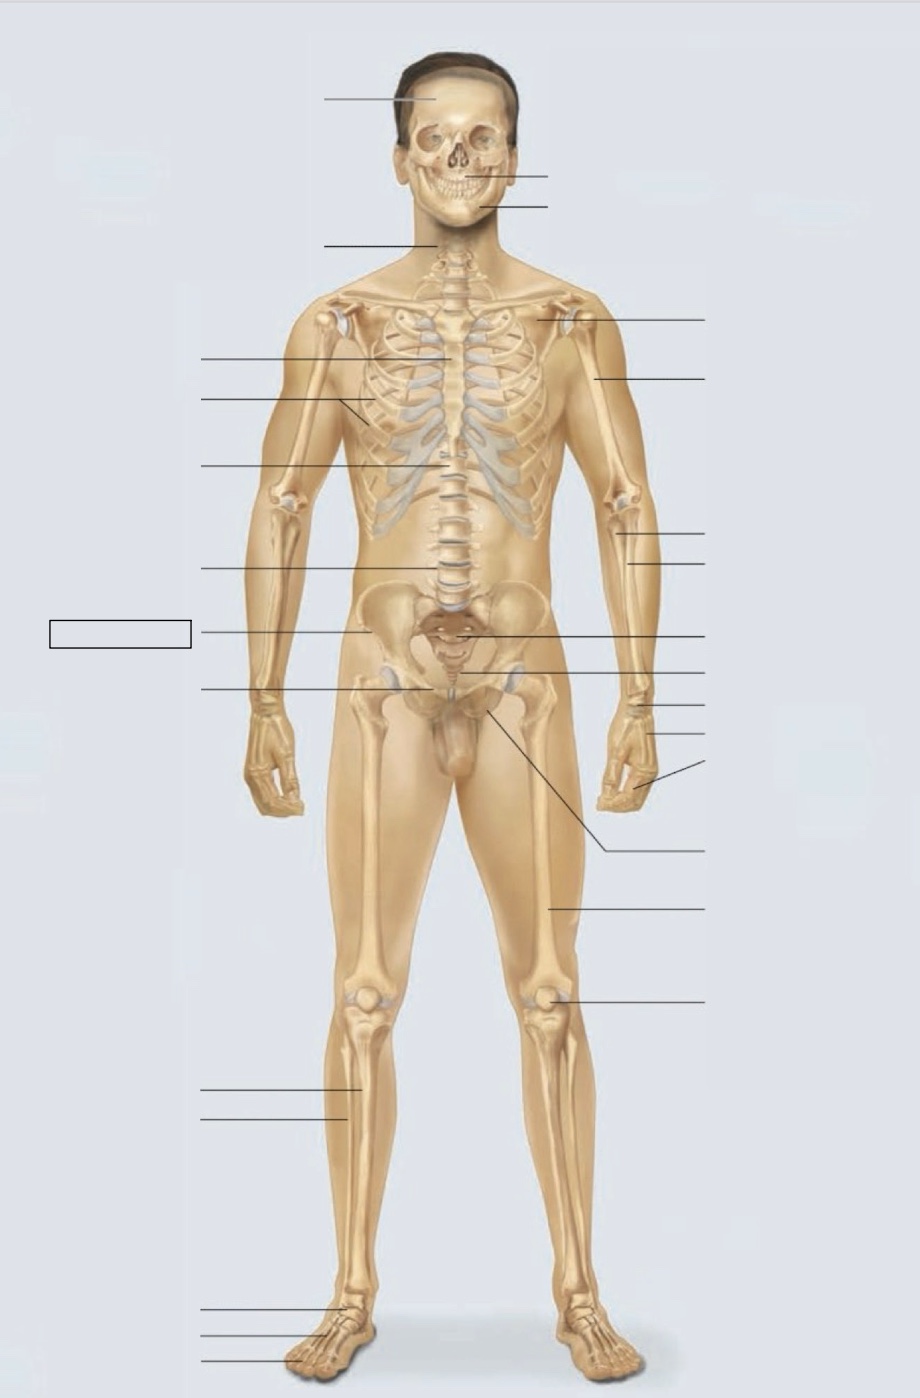

maxilla

mandible

scapula

humerus

ulna

radius

sacrum

coccyx

carpals

metacarpals

phalanges

ischium

femur

patella

phalanges

metatarsals

tarsals

fibula

tibia

pubis

ilium

lumbar vertebrae (L4)

thoracic vertebrae (T11)

ribs

sternum

cervical vertebrae

skull